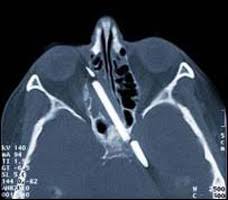

قلم الرصاص الذي كانت تحمله طوله 8سم اخترق خدها ودخل طرفه مباشرة إلى دماغها واختفى القلم كليا من سطح وجهها.

لحسن الحظ، القلم لم يصب الشريان الاورطي (وهو شريان مهم وحيوي جدا) وكان بالقرب من العصب البصري بمقدار ميليمترات قليلة، وهذا يفسر سبب بقائها على قيد الحياة.

الدكتور هانز بيربوم، اخصائي الاذن والحنجرة في مستشفى برلين العام تمكن من تحديد موقع القلم بشكل دقيق عن طريق الاشعة السينية.

قرر الجراح انه بإمكانه إزالة القلم او على الأقل جزء كبير منه، وهذا ما حصل بالفعل حيث تمكن من إزالة 6 سم من قلم الرصاص، وأبقى على طرفه بطول 2 سم لأنها كانت مغروسة بشكل قوي في مادة الدماغ والتي نمت حوله مما يجعل العملية محفوفة بالمخاطر.